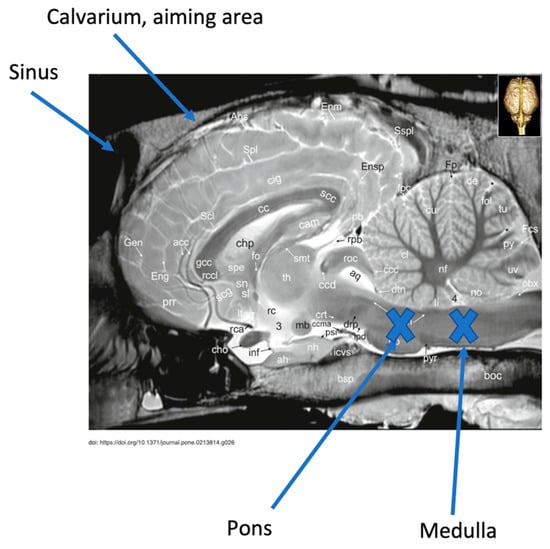

Guidelines exist describing external landmarks to target to achieve successful gunshot euthanasia [] (p. 120). Despite these guidelines, studies examining bullet trajectories in animals euthanized by gunshot have demonstrated that inadequate disruption of structures needed to ensure a quick and humane death is an issue [,,]. Breathing and cardiac rhythm are controlled by structures within the medulla oblongata and pons, making it essential to destroy this region of the brainstem to ensure that the horse cannot recover from the state of unconsciousness induced by the initial concussion of the bullet [,] (Figure 1). Failed attempts at gunshot euthanasia result in poor animal welfare and cause distress for veterinary personnel, animal owners, and members of the public. A lack of formal training programs for gunshot euthanasia has led to concerns that it is sometimes not performed accurately and is therefore inhumane []. To deem a gunshot to be a humane method and ensure horse welfare, it is critical that the bullet trajectory must be accurate. Based on the evidence, there is a need to gain proficiency with gunshot euthanasia prior to performing the procedure on animals in the field.

Figure 1. Mid-sagittal MRI image of horse head illustrating the area of brain stem, pons, and medulla oblongata that must be destroyed to achieve humane gunshot euthanasia. Image adapted from Schmidt M, et al. [].

Aiming landmarks on the model include (as described by Shearer and as referenced by Leary et al.) 1–2 inches above the intersection of two lines running from the lateral canthus of the eye to the base of the opposite ear ([] (p. 120), []) and, according to Lund et al., along the sagittal crest of the head where the two temporalis muscles form an inverted V [] (Figure 2a,b). In the model, achieving the correct aiming angle at the target formed by intersection of the X or the inverted V results in activating the laser sensor embedded in the position of the medulla or the pons, respectively (Figure 1).